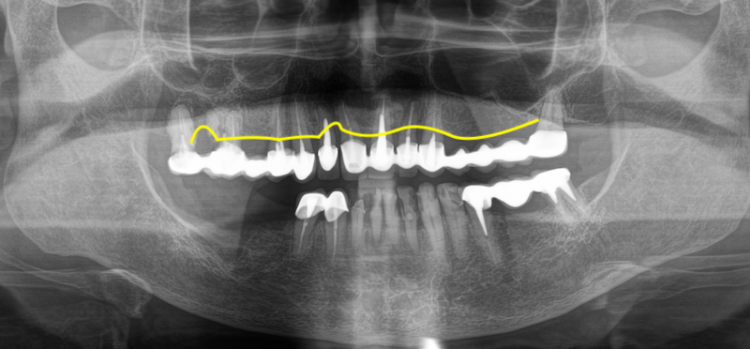

Пародонтоз — это дистрофическое заболевание тканей пародонта, то есть структур, которые удерживают зуб в челюсти. К этим тканям относятся десна, периодонтальная связка, цемент корня и альвеолярная кость. Для этого состояния характерны постепенные изменения в опорном аппарате зуба. Костная ткань медленно уменьшается в объёме, десна могут отступать, оголяются шейки зубов, появляется повышенная чувствительность. На рентгене часто видно равномерное снижение высоты кости вокруг зубов.

По внешним симптомам не всегда можно точно определить тип поражения пародонта. Окончательный диагноз устанавливают после осмотра, пародонтологического обследования и рентгенологической оценки состояния костной ткани.

Клиническое и рентгенобследование

Перед имплантацией проводят полную диагностику. Врач оценивает кровоточивость дёсен, глубину пародонтальных карманов, уровень прикрепления тканей и подвижность зубов. Далее выполняют компьютерную томографию (КЛКТ), которая позволяет измерить высоту и толщину альвеолярной кости, определить её плотность и оценить анатомические структуры — нижнечелюстной канал или гайморову пазуху.